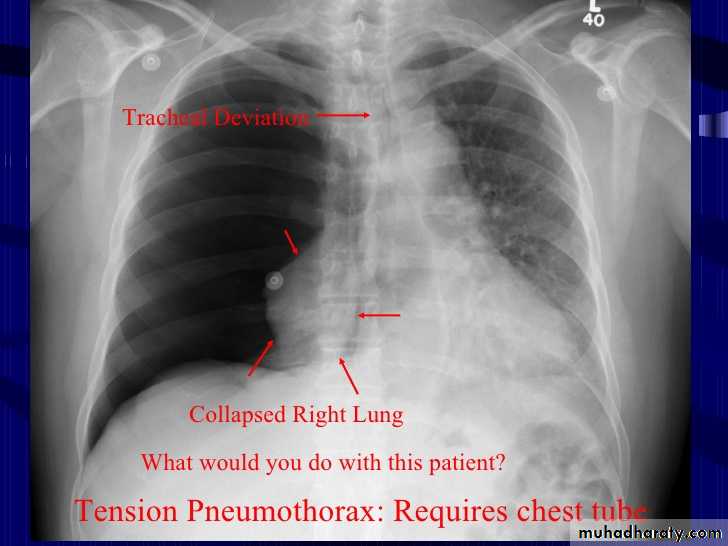

Tension pneumothorax

57. tension pneumothorax right sided aspect